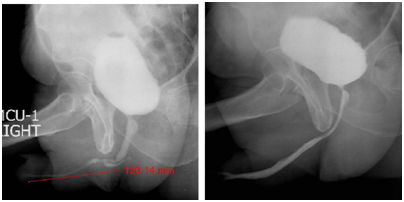

Patient is placed in social lithotomy position with Allen stirrups. Perioperative broad spectrum antibiotics are administered. Small caliber endoscopy is performed to evaluate the urethra. Gide wire is placed and methylene blue is instilled in the urethra. Midline perineal incision in made and layers dissected. (Figure 1) One sided (usually left as the surgeon is right handed) is carried out and the urethra is mobilized. (Figure 2) Penile invagination is performed. (Figure 3) Urethra is opened at 12 o’clock across the stricture. (Figures 4,5) Oral mucosal grafts are harvested simultaneously using a second team. Meatotomy is performed. (Figure 6). The grafts are quilted dorsally and urethral closure is performed using absorbable sutures (4.0 vicryl) Grafts are applied from the meatus to the proximal bulbar urethra. (Figures 7,8) Closure of the urethra is performed over a size 14 indwelling urethral catheter. Catheter is left in for 4 weeks and then removed. Pericatheter urethrogram was performed in redo and complex cases. Patient is on low dose oral antibiotics for 4 weeks. Some primary cases with poor urethral plates required a two-stage approach with graft inserted as dorsal inlay in the second stage. In redo cases a ventral approach was chosen with dorsal inlay oral mucosal graft. Figures 9 and 10 depict follow up uroflow and urethrograms. A schematic representation is depicted for easy understanding (Figure 11).

Figure 10 Pre-operative and post-operative urethrogram.